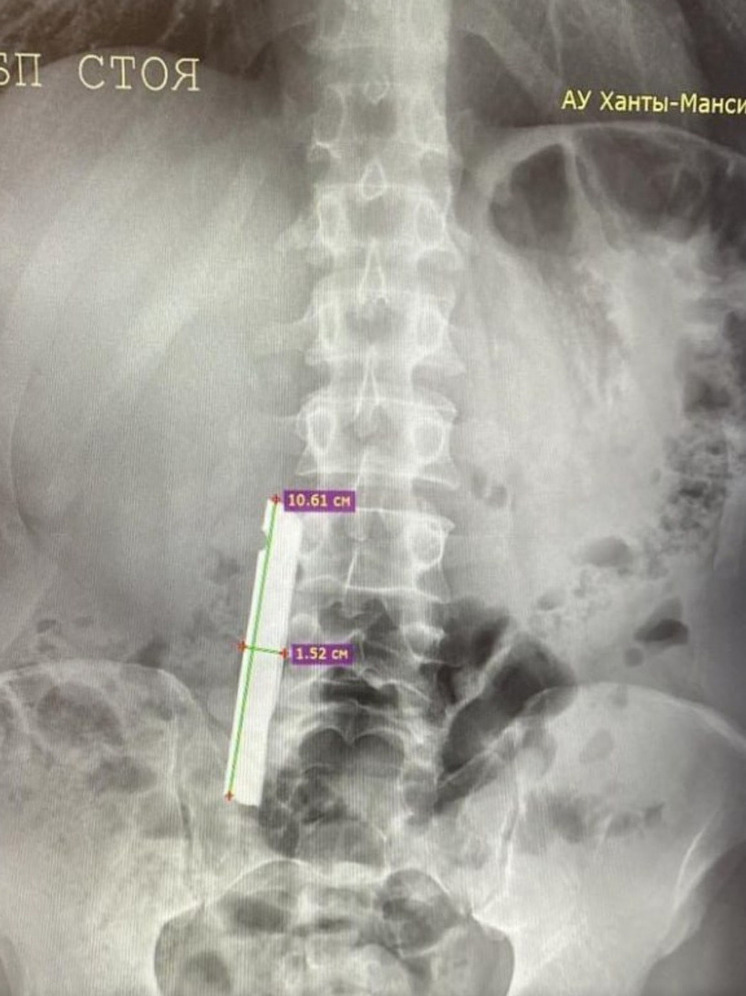

Врачи Советской районной больницы совершили успешное хирургическое вмешательство, в ходе которого извлекли крупное металлическое инородное тело из двенадцатиперстной кишки пациента. История началась с поступления больного, у которого при рентгенографическом обследовании было обнаружено постороннее тело в верхних отделах желудочно-кишечного тракта.

Экстренная диагностика с помощью эзофагогастродуоденоскопии (ЭГДС) позволила точно определить местоположение металлического предмета — он находился в двенадцатиперстной кишке. На первом этапе операции специалистам удалось переместить инородное тело в желудок, однако дальнейшие попытки его извлечения не принесли желаемого результата.

Заведующий хирургическим отделением Иван Папалуца отметил особую сложность проведённой операции. По его словам, трудности были связаны с крупными размерами инородного тела, его специфическим расположением и острыми краями, которые затрудняли манипуляцию инструментами. Успех операции, по мнению врача, стал возможен благодаря двум ключевым факторам: наличию круглосуточной эндоскопической службы, позволяющей оказывать помощь пациентам в кратчайшие сроки, и слаженной командной работе медицинского персонала. Особую благодарность заведующий отделением выразил медицинским сёстрам Марине Гатиятовой и Галине Поповой за их профессионализм и помощь в проведении операции.